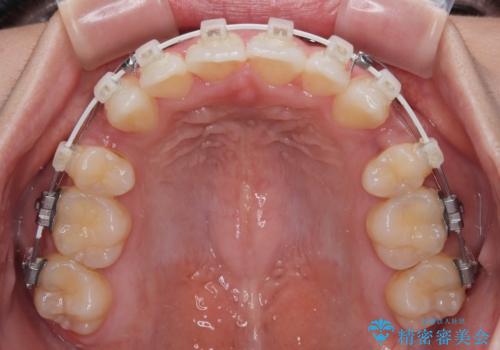

- 審美装置

- 1年10ヶ月

- 10-30回

上下左右第一小臼歯4本を抜歯し、ワイヤー装置にて口元を引っ込めるよう矯正治療を行うこととしました。